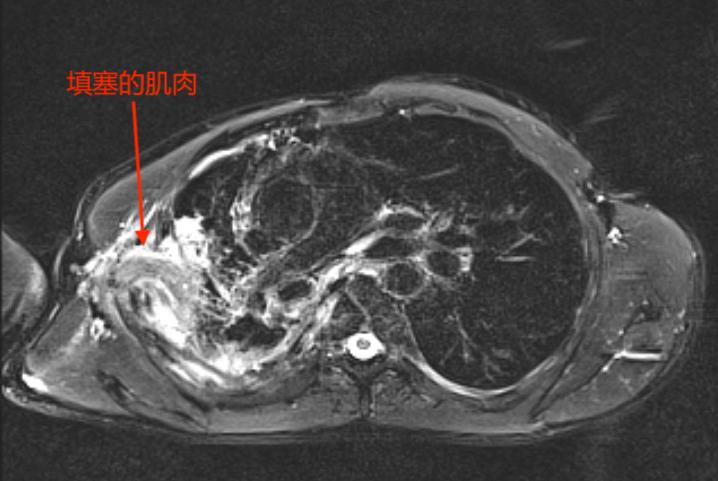

入院后,胸部CT检查提示“右上胸腔见团状包裹积气积液,局部与支气管相通,引流管留置。”随后呼吸科胡蕙蕙副主任医师又给杜先生进行了支气管镜检查,发现“右上叶尖段可见瘘口,透过瘘口甚至可见胸腔的两条引流管。”

检查结果出来后,陈医师踟躇了一下,封堵支气管瘘口不难,但如何防止瘘口复发和彻底消灭脓腔是一个难点。

手术按部就班地进行着,顺利地进行支气管瘘口封堵,然后是胸腔镜清创,就差沈医师的肌肉瓣手术了。

起初,沈医师决定用体积大、血运又非常丰富的背阔肌来填塞胸腔。

然而,手术总是存在各种变化。沈医师发现,多年的肺部疾病使杜先生丧失了大部分劳动能力,肌肉严重萎缩,单独用这块肌肉填塞胸腔,远远不够。

医生的智慧显得尤为关键,经验丰富的他当机立断,马上调整手术方案,选择增加背阔肌和胸大肌两组肌瓣联合填塞关闭胸腔。